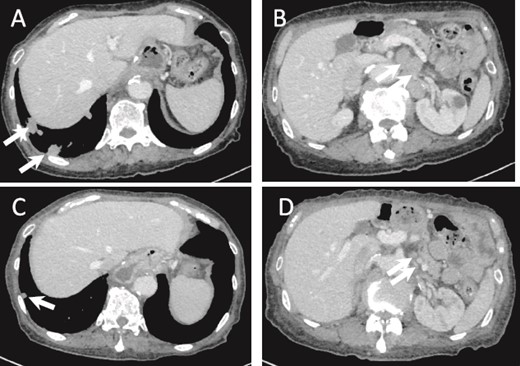

(a) CT image 5 months after surgery. Multiple lung metastases are seen (arrows). (B) Intra-abdominal lymph node metastasis is shown (arrows). (C, D) Lung and lymph node metastases after one cycle of chemotherapy show PR (arrows).